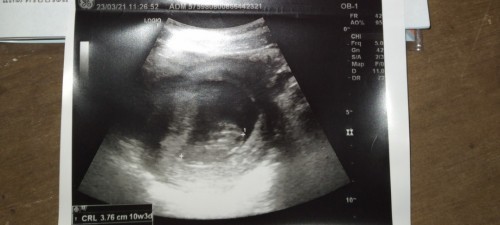

10+3ตอนนี้12